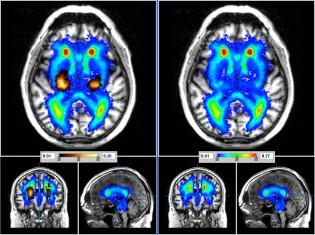

£400 could provide a short MRI scan for a research participant

• MRI scans are often used in neurological research studies because they are safe and painless for the participant, and can show doctors and scientists an incredible amount of information about the brain.

£800 could provide more detailed MRI scan for a research participant

• Specialised scans play a crucial role in developing image analysis methods by using more detailed medical images. Yet, some scans take longer time and cost more.